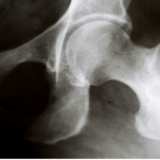

股関節包は、大腿骨頭と寛骨臼を包み込むように覆う強靭な線維性の袋状組織です。

■ 2. 股関節包の解剖学的特徴

股関節包は前方・後方・上方・下方で厚さや強度が異なります。